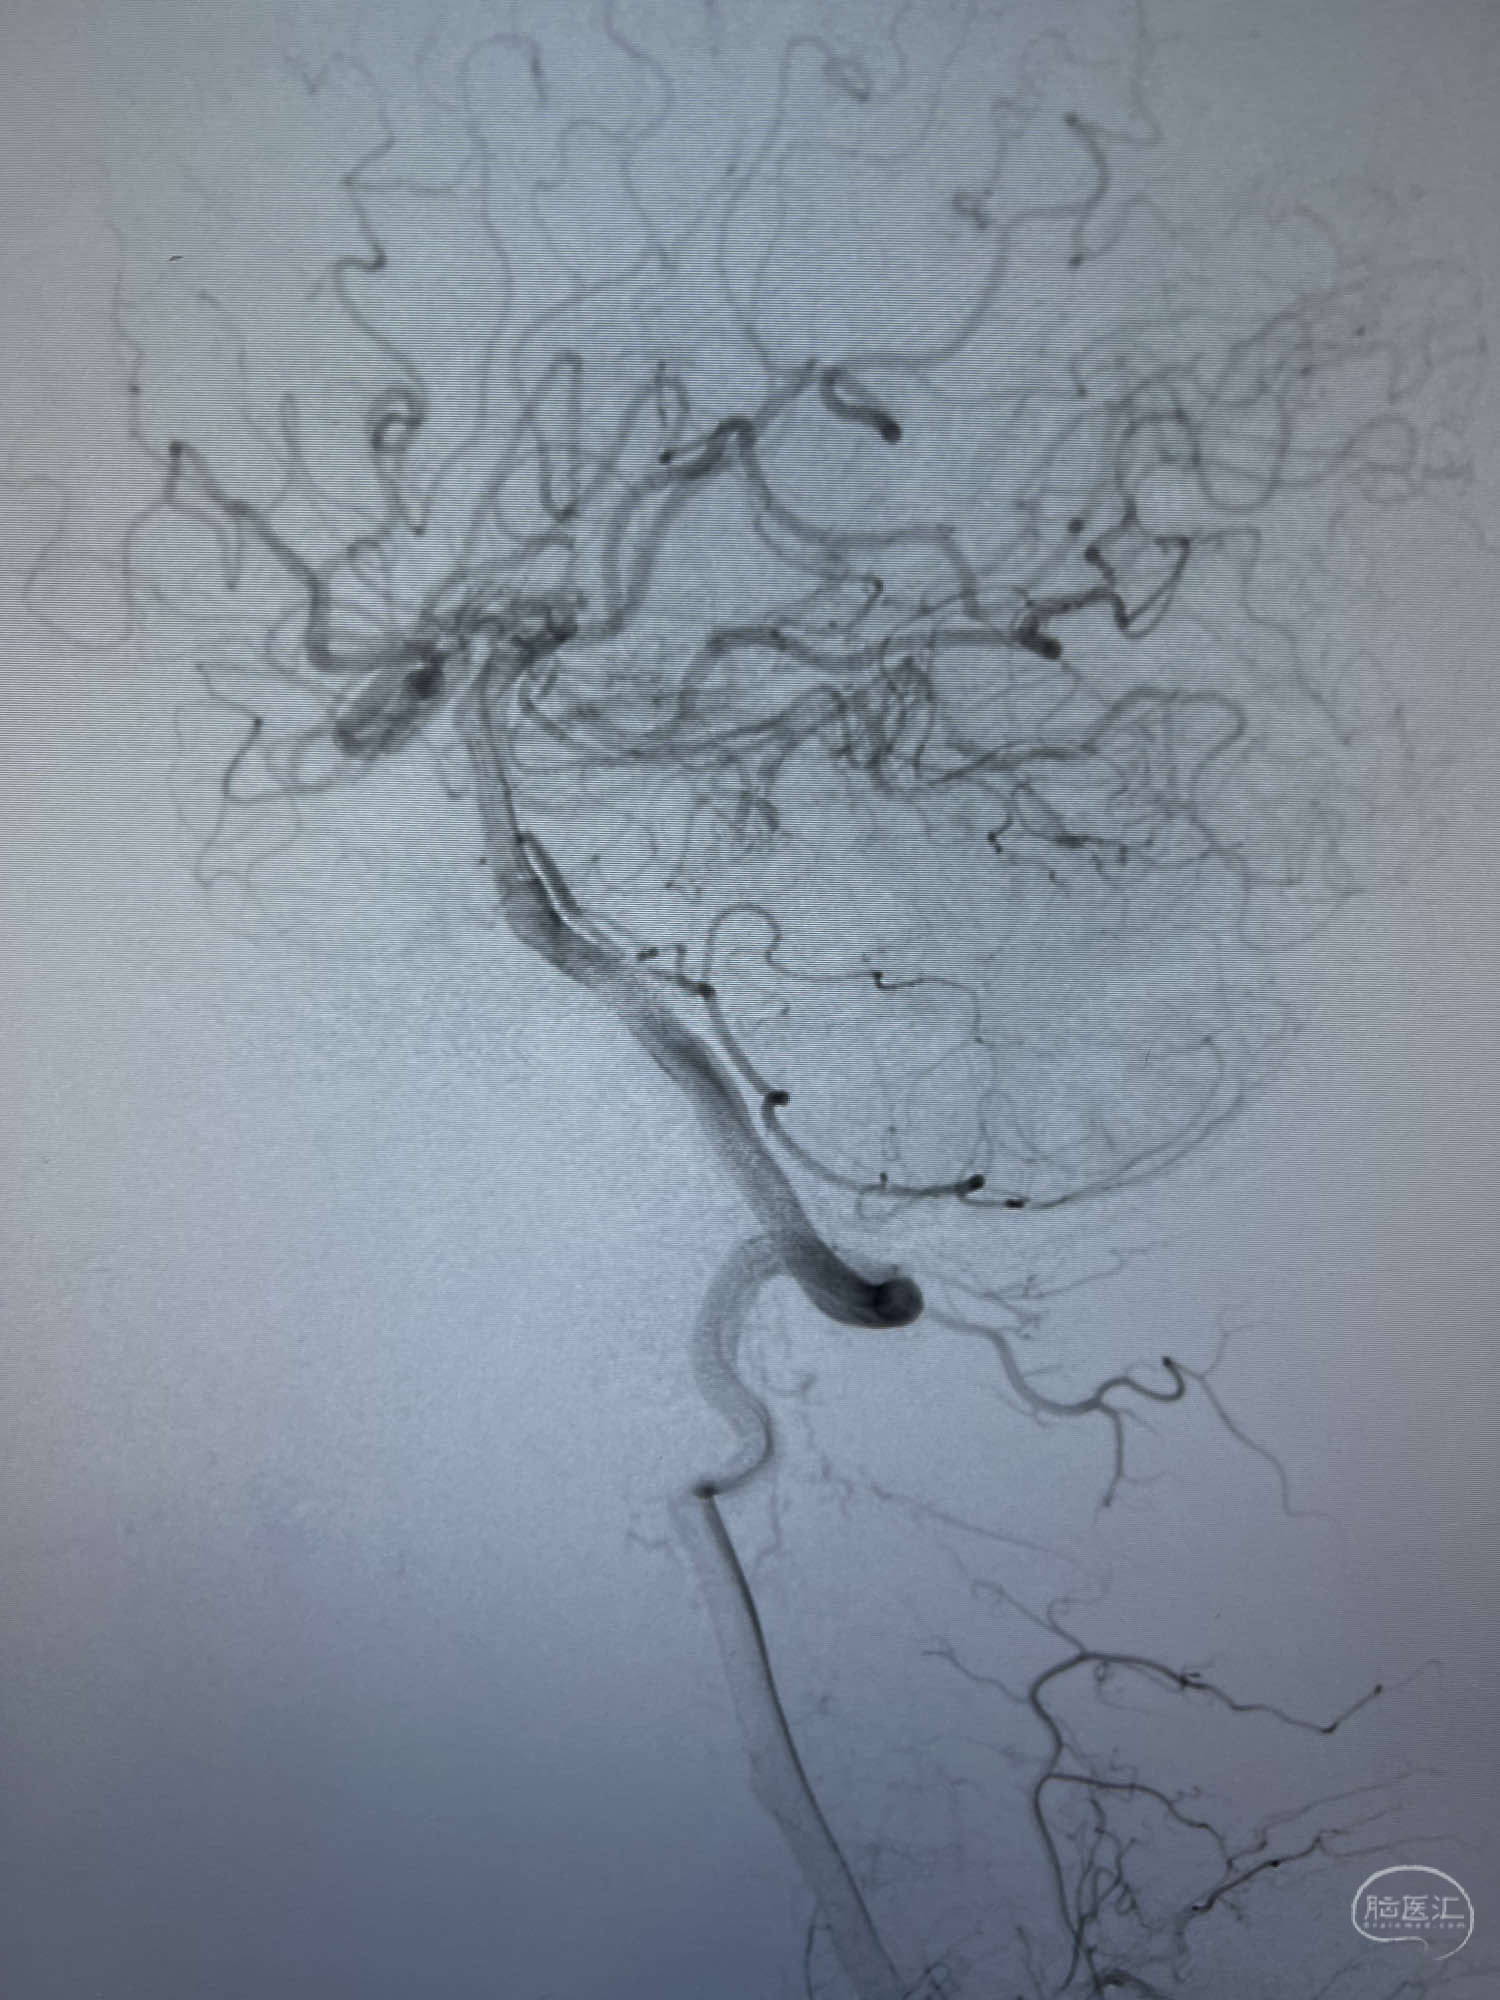

患者:LXS,M53Y,以“间断头晕头痛1周”为主诉入院,既往有高血压病及长期吸烟史。在当地医院行头颅CT未见异常,头颅MRA示右侧大脑中动脉M1段末端动脉瘤,左侧颈内动脉闭塞,交通动脉开放。

DSA示:左侧颈内动脉眼动脉段以远闭塞,后交通动脉开放,椎基底动脉通过后交通动脉代偿左侧大脑中动脉区域,右侧发出双侧大脑前动脉,右侧大脑中动脉M1末端宽颈动脉瘤,大小约4.3mmx4.6mm。